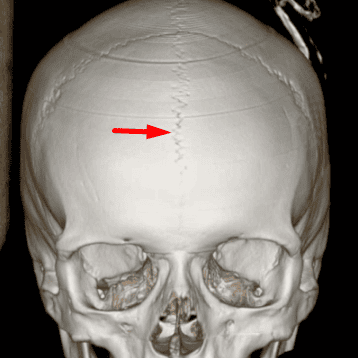

Metopic Suture

Case 17